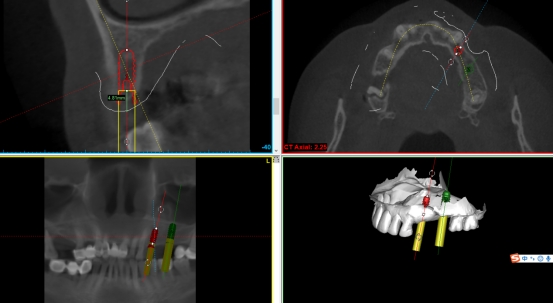

数字化种植导板是通过导板设计软件对CBCT、口扫等一系列数据的系统性分析,辅助口腔种植位点的设计,然后通过3D打印技术等途径进行导板生产,从而实现精准定位的种植手术装置。

简单来讲,数字化种植外科导板(简称导板),是将术前软件设计的种植方案,精确转移至患者口内的个性化手术辅助配件。

在数字化种植导板下的外科手术更加精准。种植体植入方向、位置、角度、深度等一目了然,即可将种植体精准植入到最佳位置,获得更优异的临床效果,手术安全性更高。